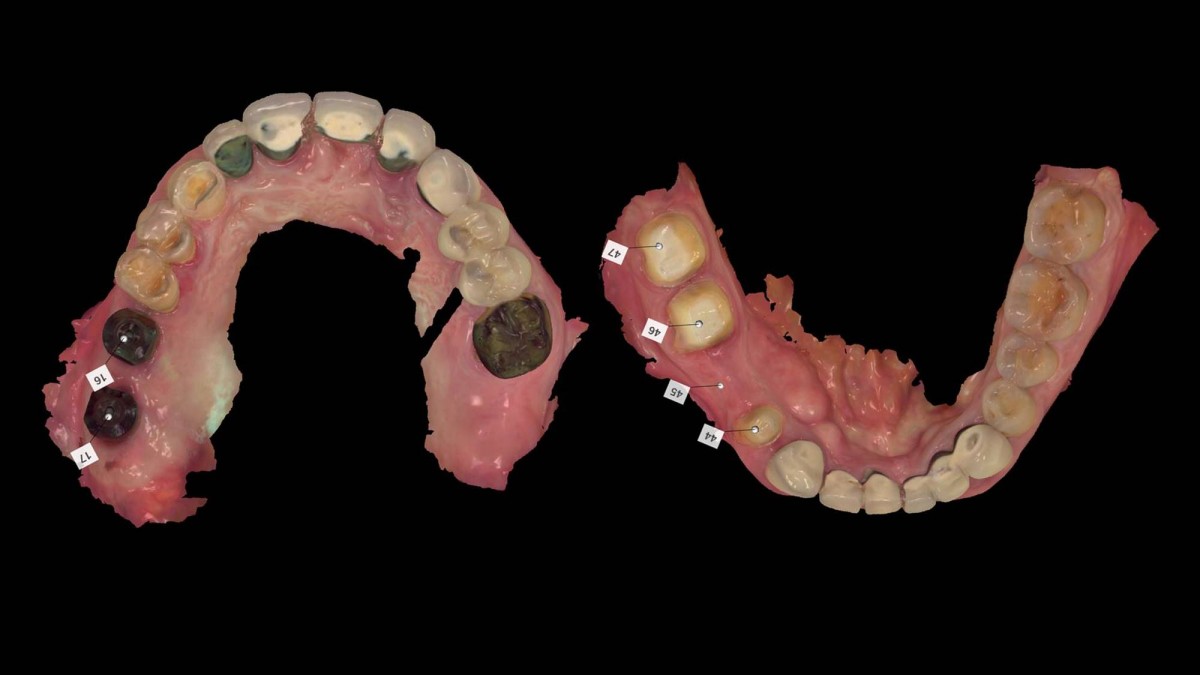

Socket Lift and Implant Placement in the right maxilla.

<GCacg> A 56-year-old male patient complained of pain in the right upper and lower jaws. And he wanted the upper first molar to be pulled out first.